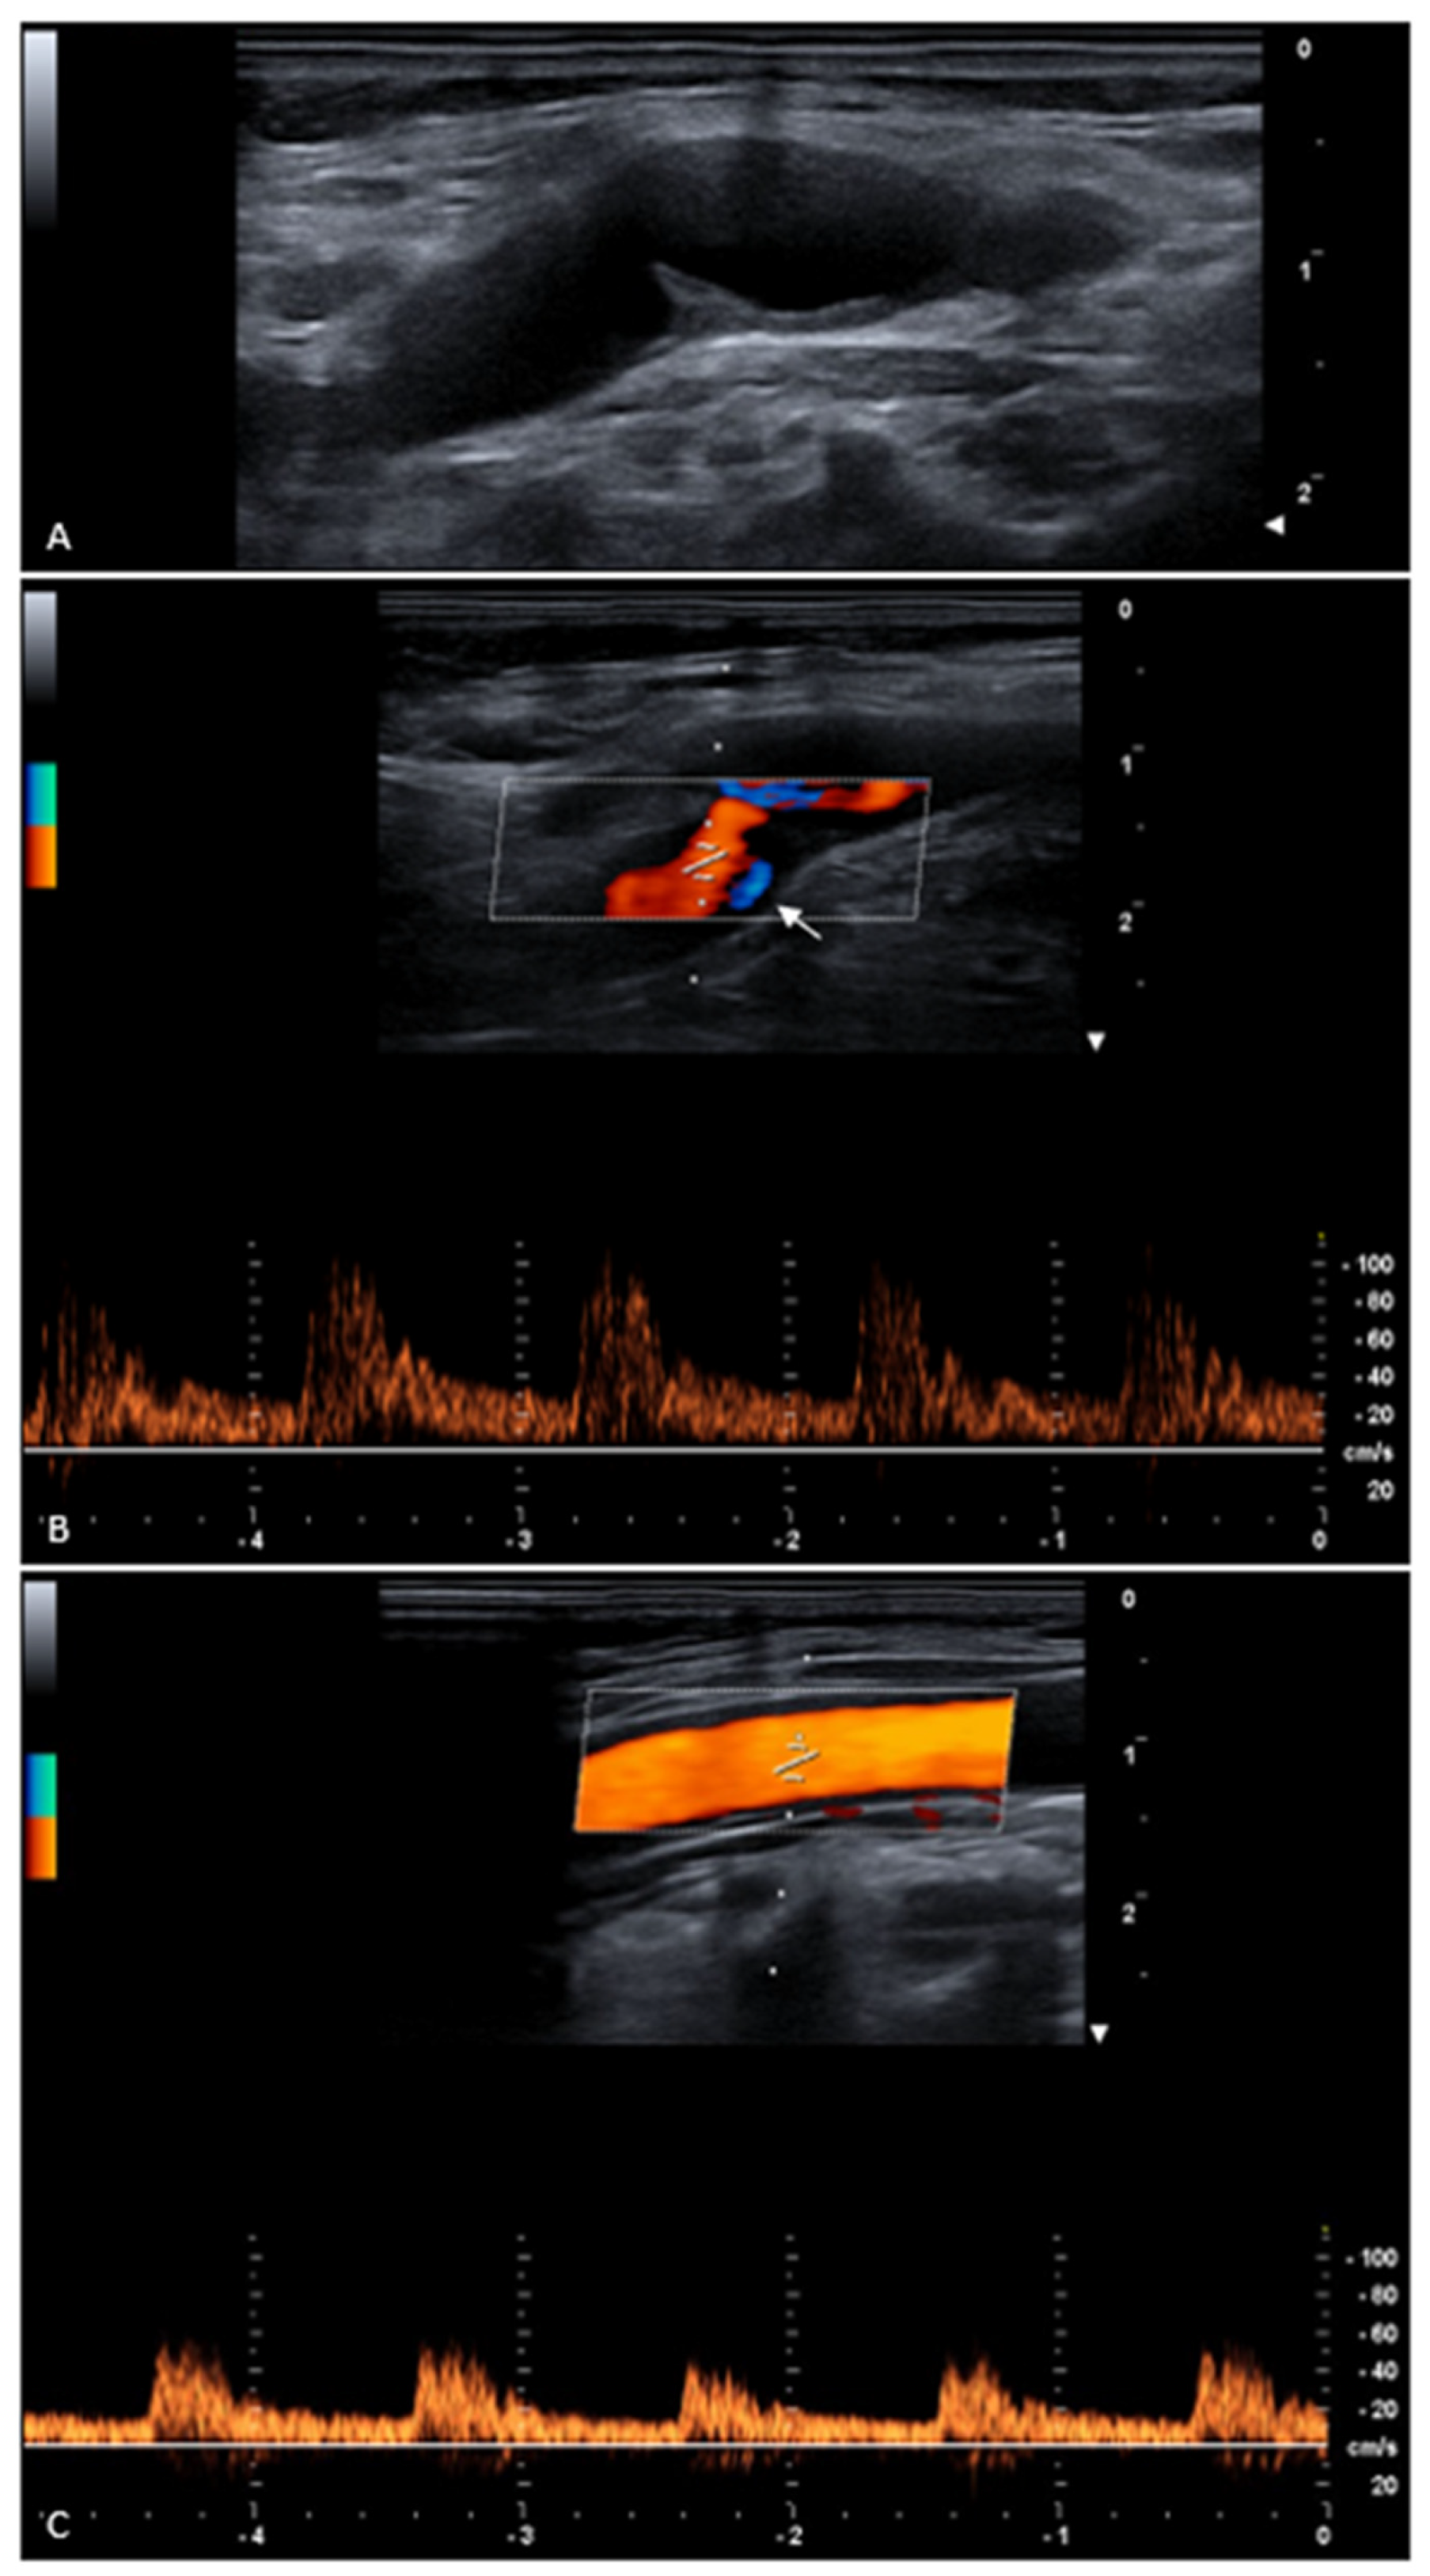

- We performed B-mode and Doppler ultrasound to diagnose the carotid web, and these techniques are recognized as valuable tools for carotid web diagnosis, particularly the longitudinal view [1,15,16]. Microvascular imaging can be useful for carotid web detection, particularly for very thin ones [14]. Contrast-enhanced ultrasound can help detect atherosclerotic plaques and thrombosis associated with carotid webs [17]. However, other previously published studies suggested that computed tomography and magnetic resonance imaging could detect carotid webs better [18]. Digital subtraction angiography has been reported by some as the gold-standard imaging modality for carotid web detection, and it can show contrast stagnation and its duration, but it is an invasive technique not recommended for diagnosis [18,19]. However, the lack of knowledge could lead to misdiagnosis and missed diagnosis with all diagnostic techniques [20].

- Not as many carotid webs have been described in the literature with hemodynamic effects. In fact, in a case series of 24 patients with carotid webs, no one showed those effects [15]. Another study reported that, in 94% of patients, the carotid stenosis was less than 50% [21]. Moreover, a previously published article reported that 7 out of 68 carotid webs showed at least 50% stenosis [22].

- In our patient, the carotid web length was 4 mm, the degree of stenosis was 50%, the common carotid artery web-pouch angle was 67°, and the common carotid artery pouch-tip angle was 93°, which are potential morphological high-risk features.